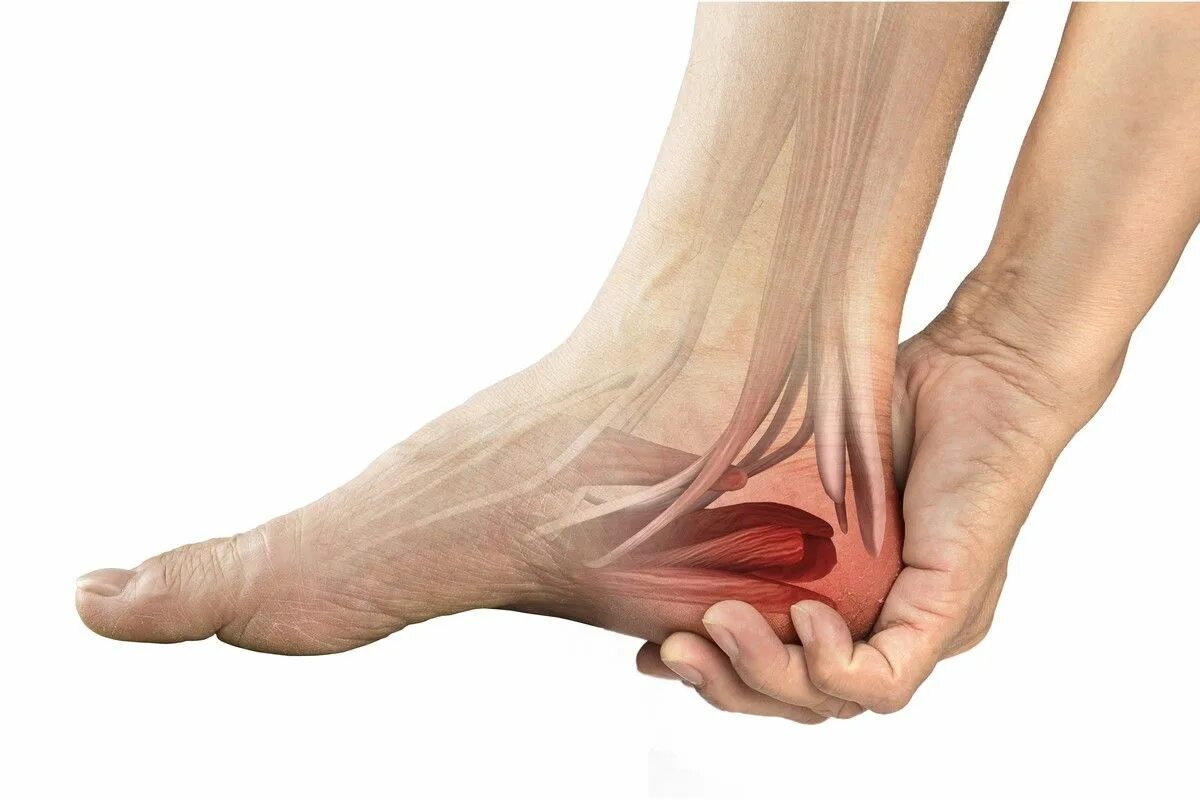

Пяточный фасцит